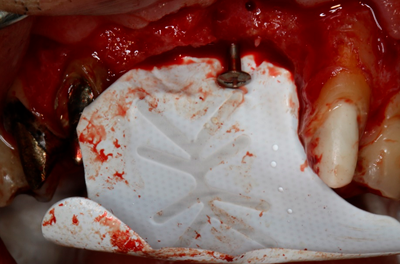

As figuras, abaixo, demonstram 3 exemplos clínicos de ROG vertical, onde foi utilizado osso autógeno particulado e substituto ósseo xenógeno, na proporção 1:1, cobertos com a membrana Cytoplast, fixada com miniparafusos. Na figura 1, temos um caso de aumento ósseo vertical, em região posterior de mandíbula, sem utilização de parafuso tenda. Na figura 2, um outro caso de aumento vertical, também em região posterior de mandíbula, onde o uso do parafuso tenda foi essencial em uma localização do defeito, corroborando o reforço de titânio da membrana. Na figura 3, temos um caso de aumento vertical na região anterior de maxila, onde o parafuso tenda foi utilizado, em um ponto considerado crítico para reconstrução óssea requerida.

Figura 3: